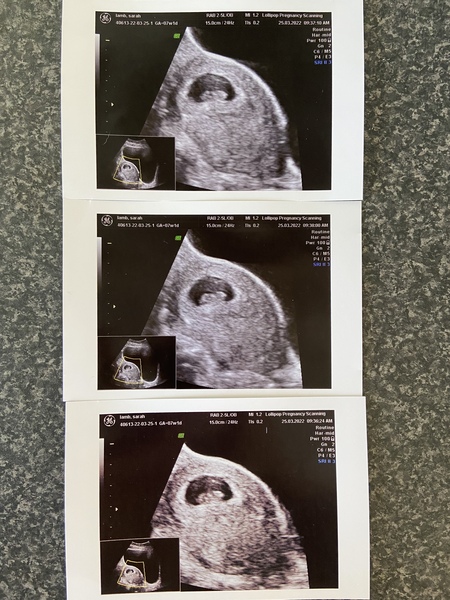

sarahj878 · 25/03/2022 13:45

Has anyone had a scan at 6 weeks 1 day please? My scan yesterday showed the gestational sac (I’m 4 weeks 5 days today) and wondering what will see at next scan. Thanks

@sarahj878 - I had a scan yesterday at 6 weeks and was able to see gestational sac, and the yolk sac, foetal pole, and also the heart pulsing. The baby looked like an engagement ring! This is the zoomed out image (zoomed in was visible and you can see the heart beating, but it's very low focus).

sarahj878 · 25/03/2022 14:09

@tigger2022 congratulations, that’s so exciting! Are you well into 6th week or were you exactly 6 weeks yesterday? Really hope we get to see everything we need to see at the next scan, feels like a long wait. I got some blood tests back today and my HCG is more than doubling so am hoping that is a good sign Smile

sarahj878 · 25/03/2022 15:19

@tigger2022 thanks that’s so good to know! Aw I bet you can’t wait. Are you having private scans?

sarahj878 · 25/03/2022 15:21

@TTCIrishlass it was me who had the 4 week 4 day scan yesterday. They didn’t give me a picture. Are you also having early scan?

sarahj878 · 25/03/2022 15:46

@tigger2022 that’s shocking they turned you away! Glad you were able to be seen privately so soon. I had a week of implantation bleeding before I knew I was pregnant so ended up having a scan to check if anything was the matter. Then I tested positive 2 days later but because of my spotting (which has stopped) I had my hcg levels done and they booked me a scan. I’ve got another blood test tomorrow

sarahxdx · 25/03/2022 18:27

I’ve just had my scan 7weeks and 1 day 🥰🥰